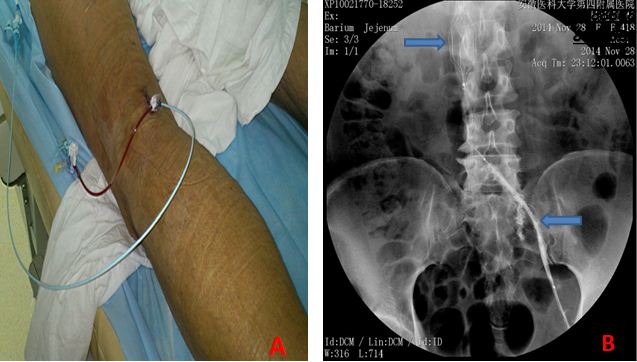

该两名患者皆为左下肢肿胀收住我科,经下肢深静脉造影检查确证为左下肢髂股静脉血栓形成。由于患者年龄较轻,考虑到永久性下腔静脉滤器置入后有引起腔静脉堵塞、血栓复发率高的缺陷,经科室讨论,在徐阿曼副院长的指导下,为患者采用了可回收式滤器置入,同时采用导管接触性溶栓的方法为患者实施治疗。导管接触性溶系将溶栓导管置于发生血栓的深静脉内,使溶栓药物直接作用于血栓,相比较以往的外周系统溶栓能显著提高血栓的溶解率,降低静脉血栓后遗症的发生率。溶栓治疗10天后,我科室再为患者成功实施了下腔静脉滤器取出术,现两名患者皆已顺利出院。以上手术的顺利开展,标志着我院普外科在下肢深静脉血栓的诊疗技术上已达到省内领先水平。(普外科)